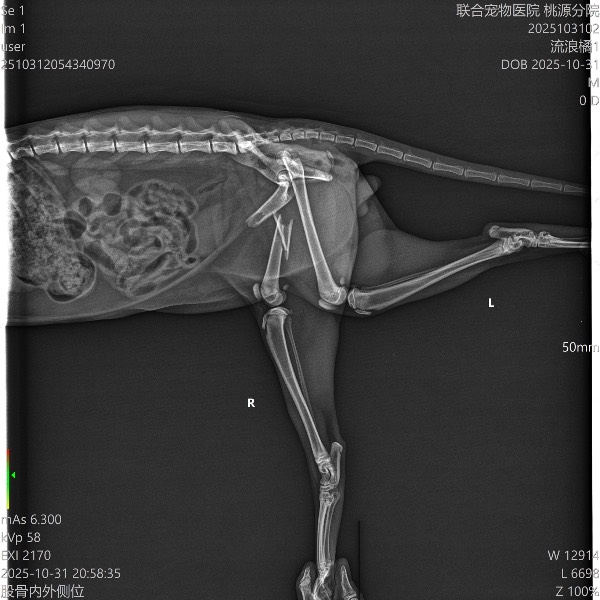

联合-桃源分院

会员卡号:6157/未审核

动物情况:地铁站口捡到的流浪猫,美短,怀孕,左眼有伤,找不到主人,先带往医院检查身体情况。

医院联络人意见:

申请时间:2025/11/04